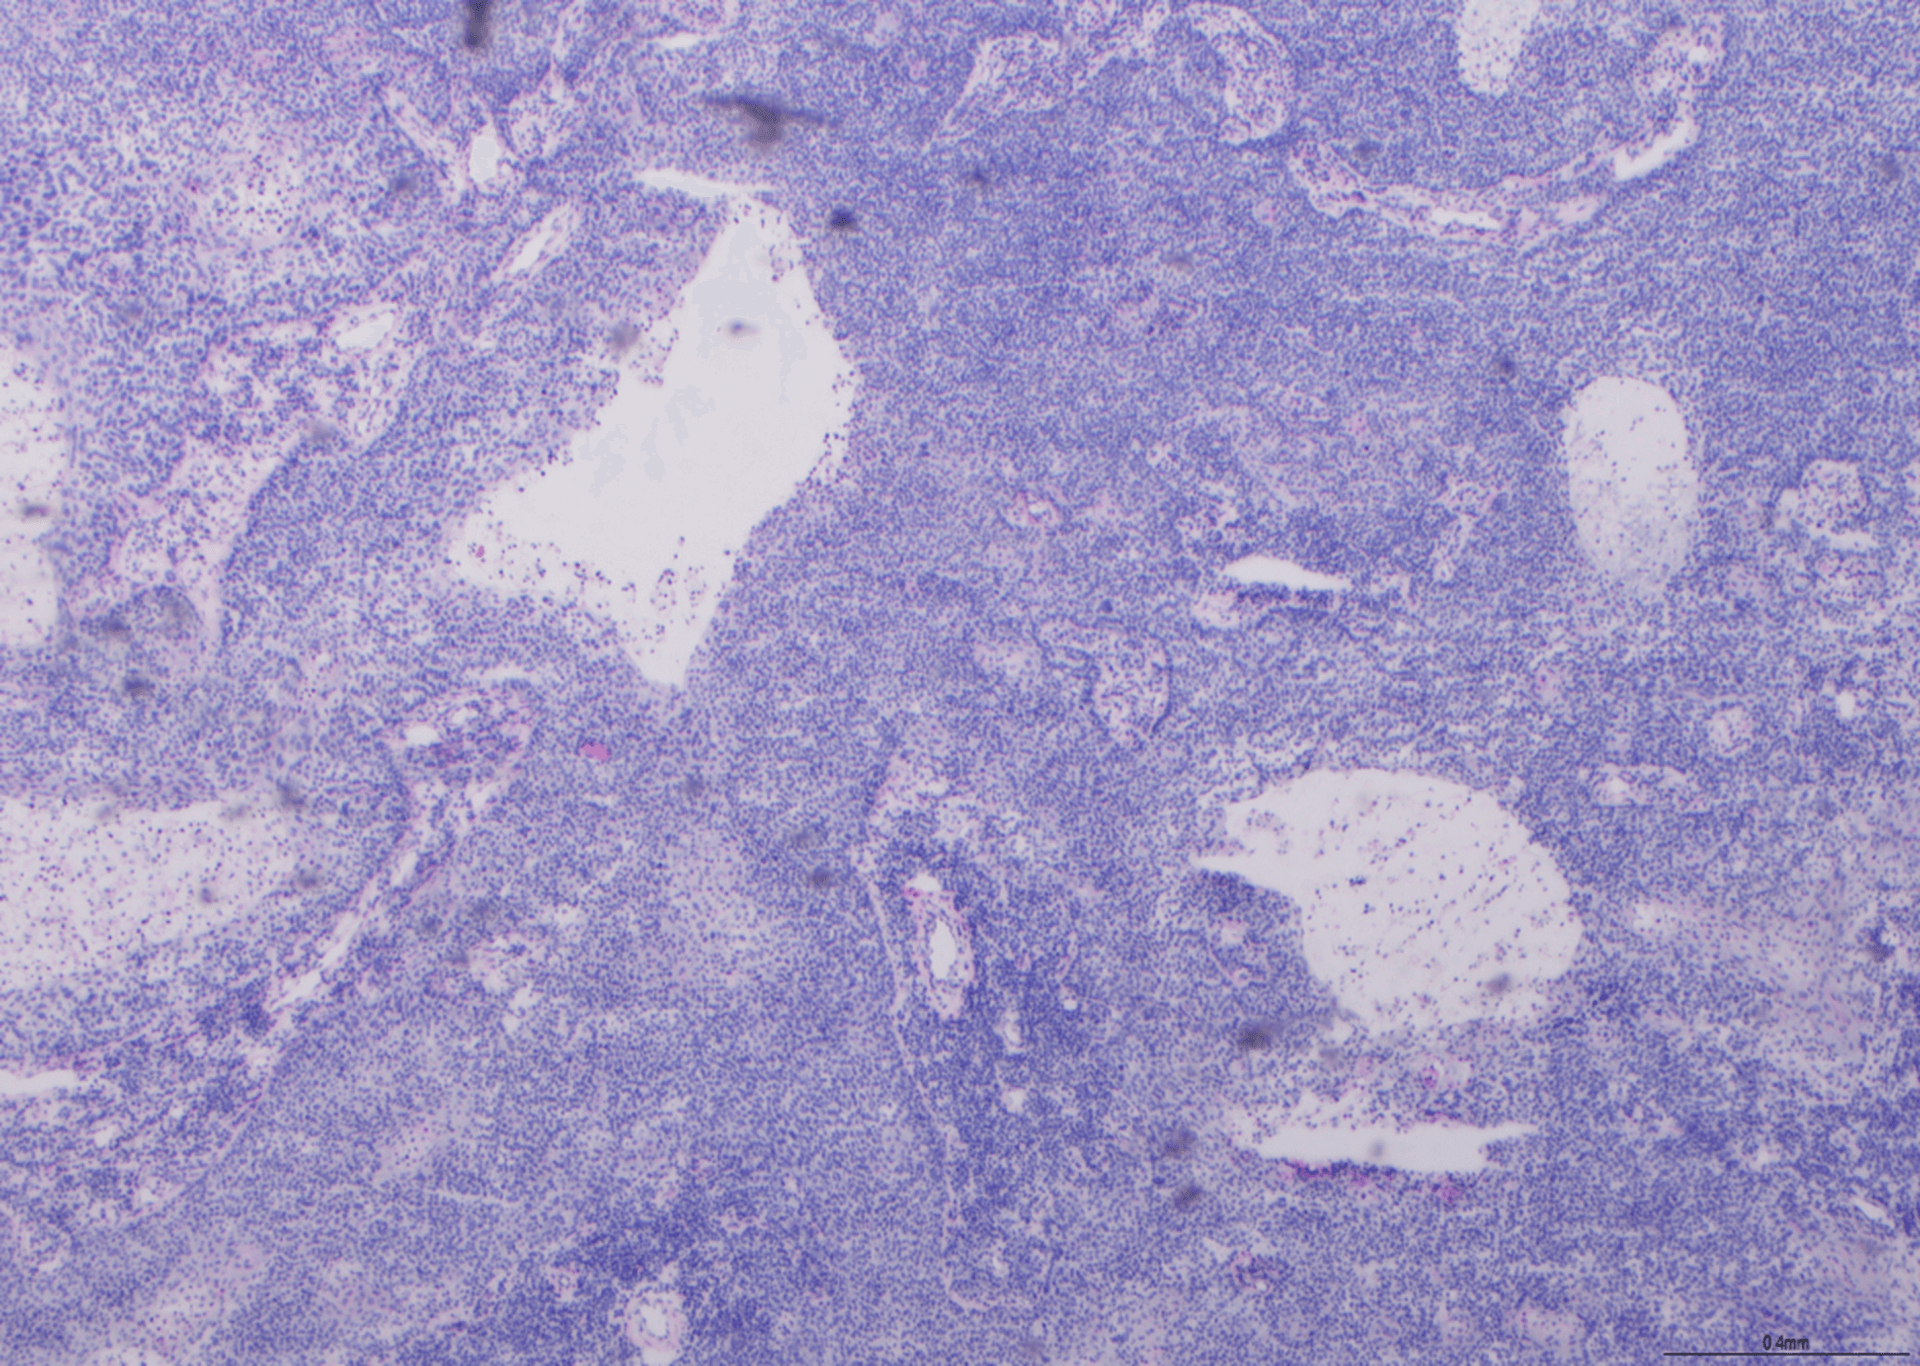

Pagbalam ng Reticulin - BMT Scheme

Ito ay isang mahusay na halimbawa ng paglamlam ng retuculin. Ang pilak ay may impregnated course at fine fiber network na may mataas na specificity. Nakakuha ito ng 9/10.